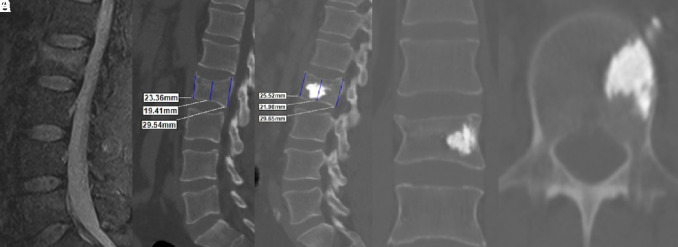

Methods: In this retrospective study, we reviewed data from 96 patients who underwent single-level unilateral kyphoplasty. The patients were categorized into 2 groups based on the cement volume injected: group 1 (cement volume "4 mL, minimum 3 mL; n=48) and group 2 (cement volume >4 mL, maximum 6 mL; n=48). The clinical outcomes, as assessed using the Oswestry Disability Index (ODI) and visual analog scale (VAS) scores, were evaluated preoperatively and then at the final follow-up 1 month postoperatively. The vertebral corpus height at the fracture level was measured at the anterior, middle, and posterior regions through sagittal computed tomography scanning.

Results: The mean age of the patients was 64.2 years in group 1 and 63.8 years in group 2. In group 1, the mean anterior vertebral height increased from 19.0 ± 3.3 mm preoperatively to 19.9 ± 3.2 mm postoperatively, whereas in group 2, it increased from 17.9 ± 3.8 mm to 19.6 ± 3.7 mm, respectively. The middle vertebral heights were 15.4 ± 2.5 mm preoperatively and 16.9 ± 2.8 mm postoperatively in group 1 and 16.0 ± 3.6 mm and 17.5 ± 3.2 mm, respectively, in group 2. Both groups exhibited significant improvements in ODI and VAS scores, with no significant di#erence between the groups. A statistically significant increase was recorded within each group for the anterior, middle, and posterior vertebral heights. However, a significantly greater increase was noted in the anterior height in group 2 compared to that in group 1 (P < .05).